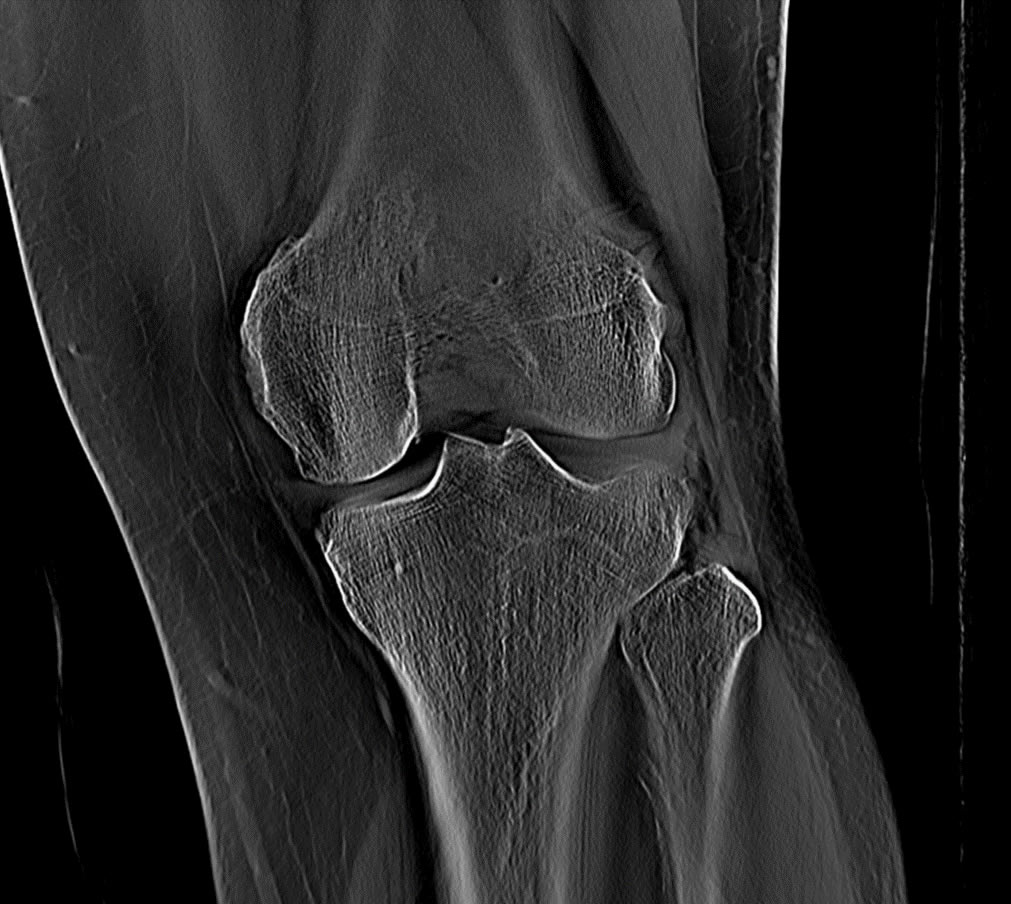

Producing many different imaging modalities

Motion corrected 2D images of morphology